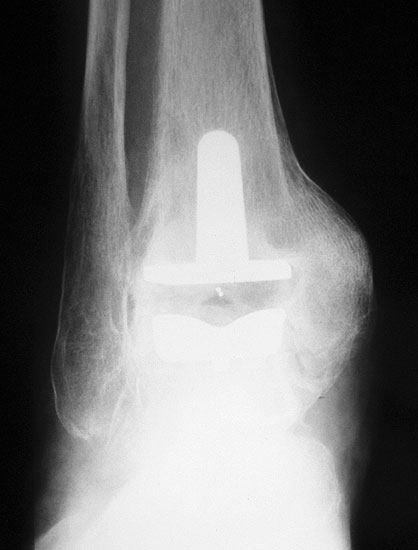

Osteosynthese eines intraoperativ frakturierten medialen Malleolus mit perkutanen Schrauben.

Abbildung 19

1. intraoperative Innenknöchelfraktur:

Mögliche Ursachen können eine zu weit medial plazierte Tibiakomponente oder eine zu weit mediale, nicht nach lateral konvergierende Sägerichtung im Rahmen der ventrodorsalen distalen Tibiaresektion sein (Abb. 19).